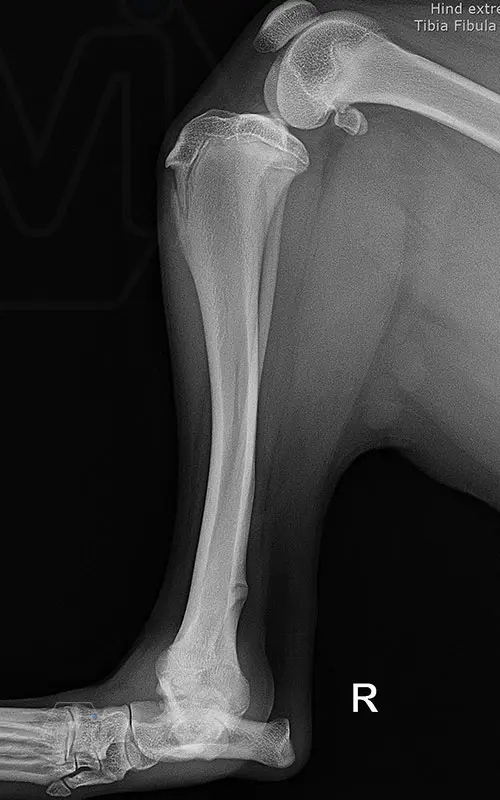

Multifunctional symmetrical long polyaxial locking plate - designed for the treatment of fractures close to joints

A special member of the polyaxial locking plate family is the multifunctional long plate, which is an extended version of the well-known symmetrical TPLO plate, with a 5-3 hole distribution. The plate also received a DCP hole to be able to create compression, and there is a mini-hole on the head end to facilitate the placement of the temporarily used K-nail. The burrs on the side facing the bone surface are intended to reduce the contact surface between the plate and the bone (limited contact).

The plate is a member of the large polyaxial locking family, suitable for 2.7-3.5-4.0 mm screws. We recommend it for fixaton of fractures close to joints, wedge osteotomies with axis correction (closing and opening), or for CWTO operations.